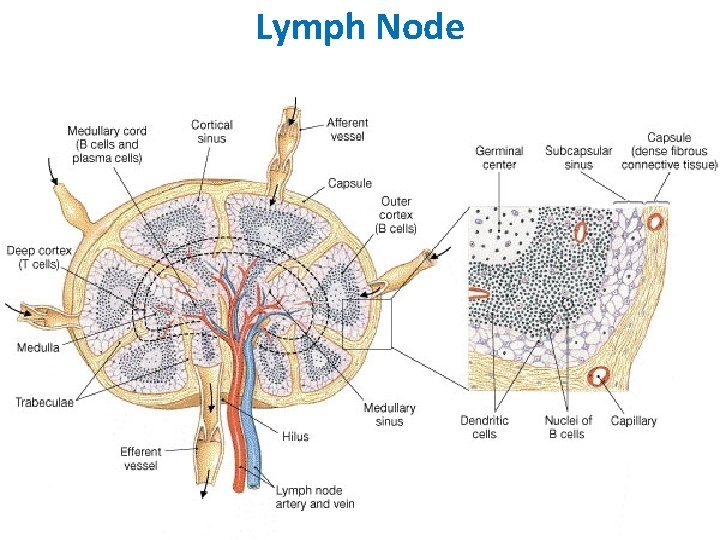

LYMPH NODES These are the smallest but most numerous encapsulated lymphoid organs. Scattered in groups along lymphatic vessels , they act as in-line filters of the lymph, removing antigens and cellular debris and adding Igs. Lymph nodes are bean-shaped structures with convex and concave surfaces. The parenchyma consists of a peripheral cortex, adjacent to the convex surface, and a central medulla lying near the depression (hilum) in the concave surface. The connective tissue capsule gives off trabeculae that penetrate between the cortical nodules and subdivide the cortex. Cortex. The cortex is dark-staining owing to the presence of tightly packed lymphocytes. These are suspended in a reticular connective tissue network and arranged as a layer of typical secondary lymphoid nodules (containing primarily B lymphocytes) with germinal centers. The cortex also contains reticular cells, antigen-presenting follicular dendritic cells, macrophages, a few plasma cells, and some helper T cells.

Medulla. Lighter staining than the cortex, the medulla is composed of cords of lymphoid tissue (medullary cords) separated by medullary sinuses. The lymphocytes are mainly small, less numerous than in the cortex. The cords are also rich in reticular cells and fibers and contain many plasma cells that have migrated from the cortex. Paracortical zone. This is the T-dependent region, lying between the cortical lymphoid nodules and the medulla. It contains mainly T lymphocytes suspended in a reticular connective tissue. B lymphocytes, plasma cells, macrophages, and antigen-presenting interdigitating dendritic cells may also be present. Lymphatic vessels. Sinuses (subcapsular, peritrabecular, medullary). Functions: 1. Filtration of lymph 2. Lymphocyte production (lymphopoiesis). 3. Immunoglobulin production.